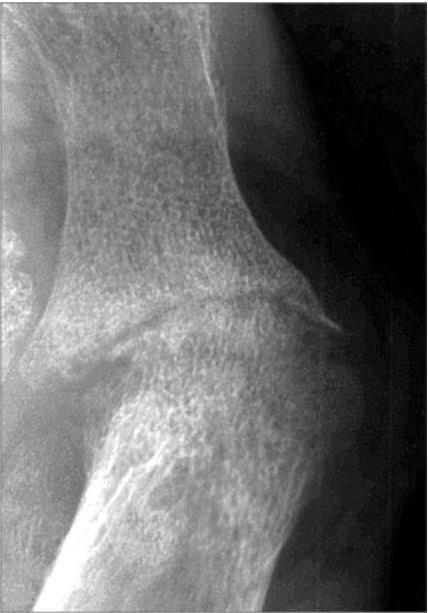

На рентгенограмме с прямым многократным увеличением отчетливо виден процесс резорбции костной ткани, образования эрозий, узур у больной с РА (рис. 13). На теплограмме воспаленного коленного сустава больной РА (рис. 14) представлено резко увеличенное тепловое излучение, вследствие увеличенного обмена паннуса. Оно буквально повторяет объем паннуса, который занимает всю суставную полость. Эта теплограмма артрита отчетливо отличается от теплоизлучения при реактивном синовите больных ОА с небольшими локальными очагами гипертермии (cм. рис. 12).

Рис. 13. Рентгенограмма I плюснефалангового сустава левой стопы больной III стадии РА

Прямое 7-кратное увеличение рентгеновского изображения. Резко выраженный диффузный остеопороз. Значительное неравномерное сужение суставной щели с истончением, разрушением замыкающей костной пластинки. Множественные глубокие краевые дефекты костной ткани с размытыми краями (эрозии), расположенные субпериостально, в зоне сустава